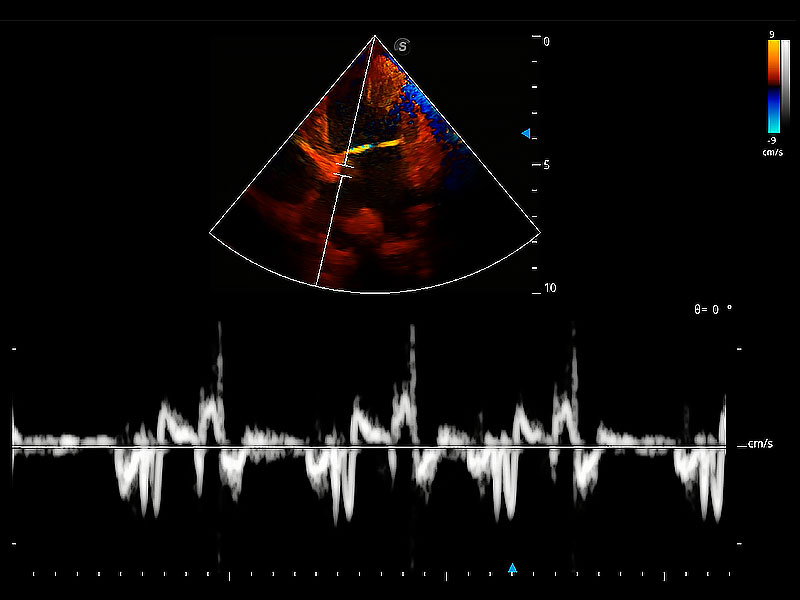

实时用颜色表示心肌组织运动,观察和定量组织的运动情況,对快速检测与评估心肌的灌注和活性、电传导及心肌收缩和舒张功能等均能提供重要的诊断信息。

随着取样门位置改变,频谱多普勒包络可进行自动眼踪测量,且可自由配置测量的参数。